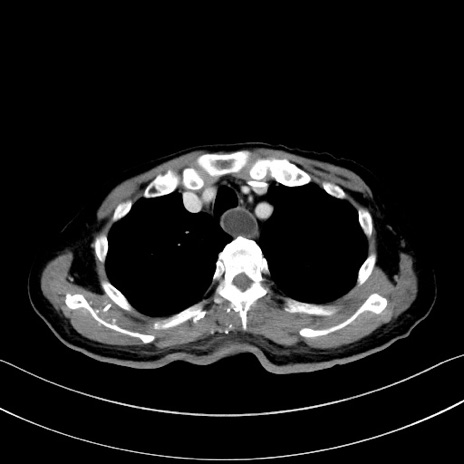

症例28(横断像)

【症例】60歳代男性

【主訴】嘔吐

【現病歴】胃癌にて胃全摘後。食思不振が悪化し、夜中に嘔吐することがある。

【既往歴】胃癌、胃全摘、脾摘、胆摘後

【データ】WBC 5900、CRP 10.56